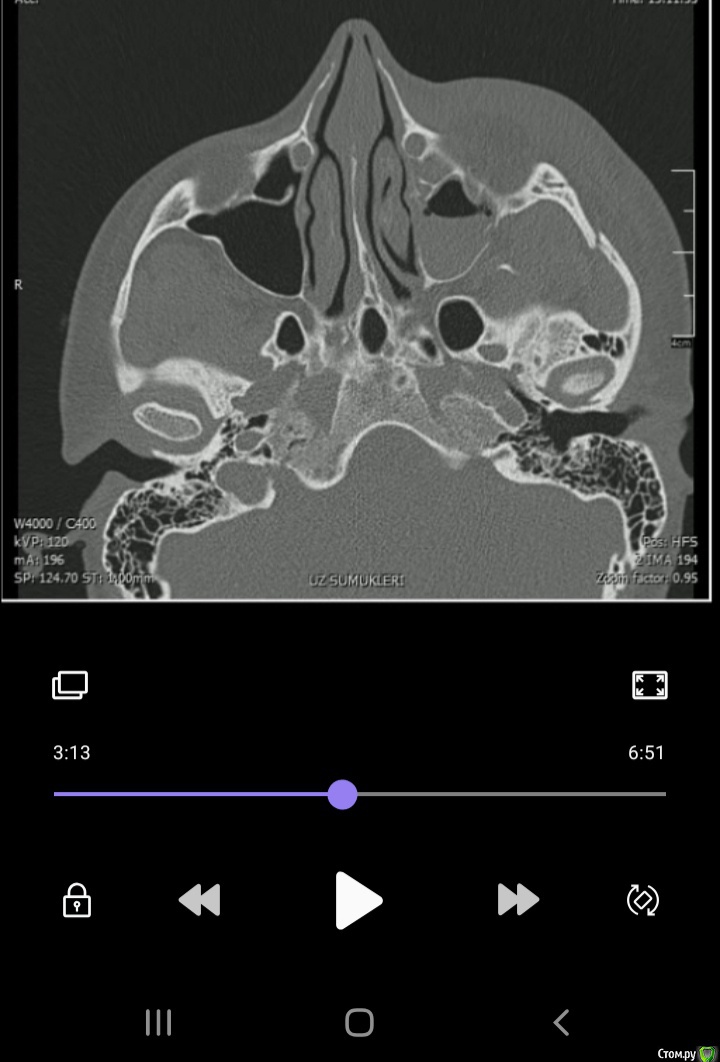

Kainat Опубликовано 22 августа, 2020 Поделиться Опубликовано 22 августа, 2020 Здравствуйте, уважаемые форумчане!У пациентки перелом скуловой кости. Жалобы на ограничение открывания рта, онемение подглазничной области. Была проведена репозиция по Лимбергу. После репозиции немножечко улучшилось открывание рта. Прошел месяц, деформации не наблюдается, однако у пациентки пока сохраняется онемение, в щечной области правда восстановилась чувствительность. Основная жалоба на ограничение открывания рта (2пальца). Может ли это быть связана с мышечной контрактурой, т.к. отек мягких тканей был очень сильным и до сих пор полностью не прошел. Данные кт прилагаются (первые три рисунка до репозиции). Благодарю заранее! Ссылка на комментарий

Irouil Опубликовано 23 августа, 2020 Поделиться Опубликовано 23 августа, 2020 Вы видите причину ограничения открывания рта? Могу выслать видео кт...Не вижу, просто без структурных причин месяц контрактуры я не встречал. Можете выложить просто на файлообменник В смысле деформации костной ткани не наблюдается, симптом ,,ступеньки" не наблюдается...Теперь ясно. По предоставленным срезам репозиция успешная. Может гематома инкапсулированная где-то, гемосинус был Ссылка на комментарий